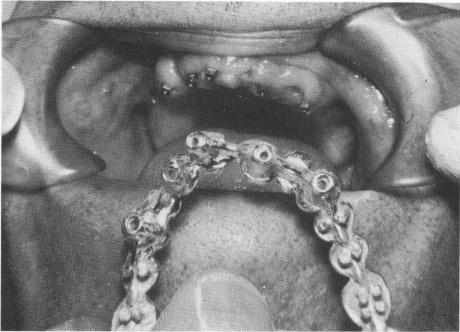

Fig. 10-248. The template was secured to the implants by screwing the small set screws through it.

vertical extensions of the template so that they were flush with it (Fig. 10-246). The template was tried in the patient's mouth (Fig. 10-247), and the small set screws were inserted through the template and into the internal threads of the implants (Fig. 10-248).